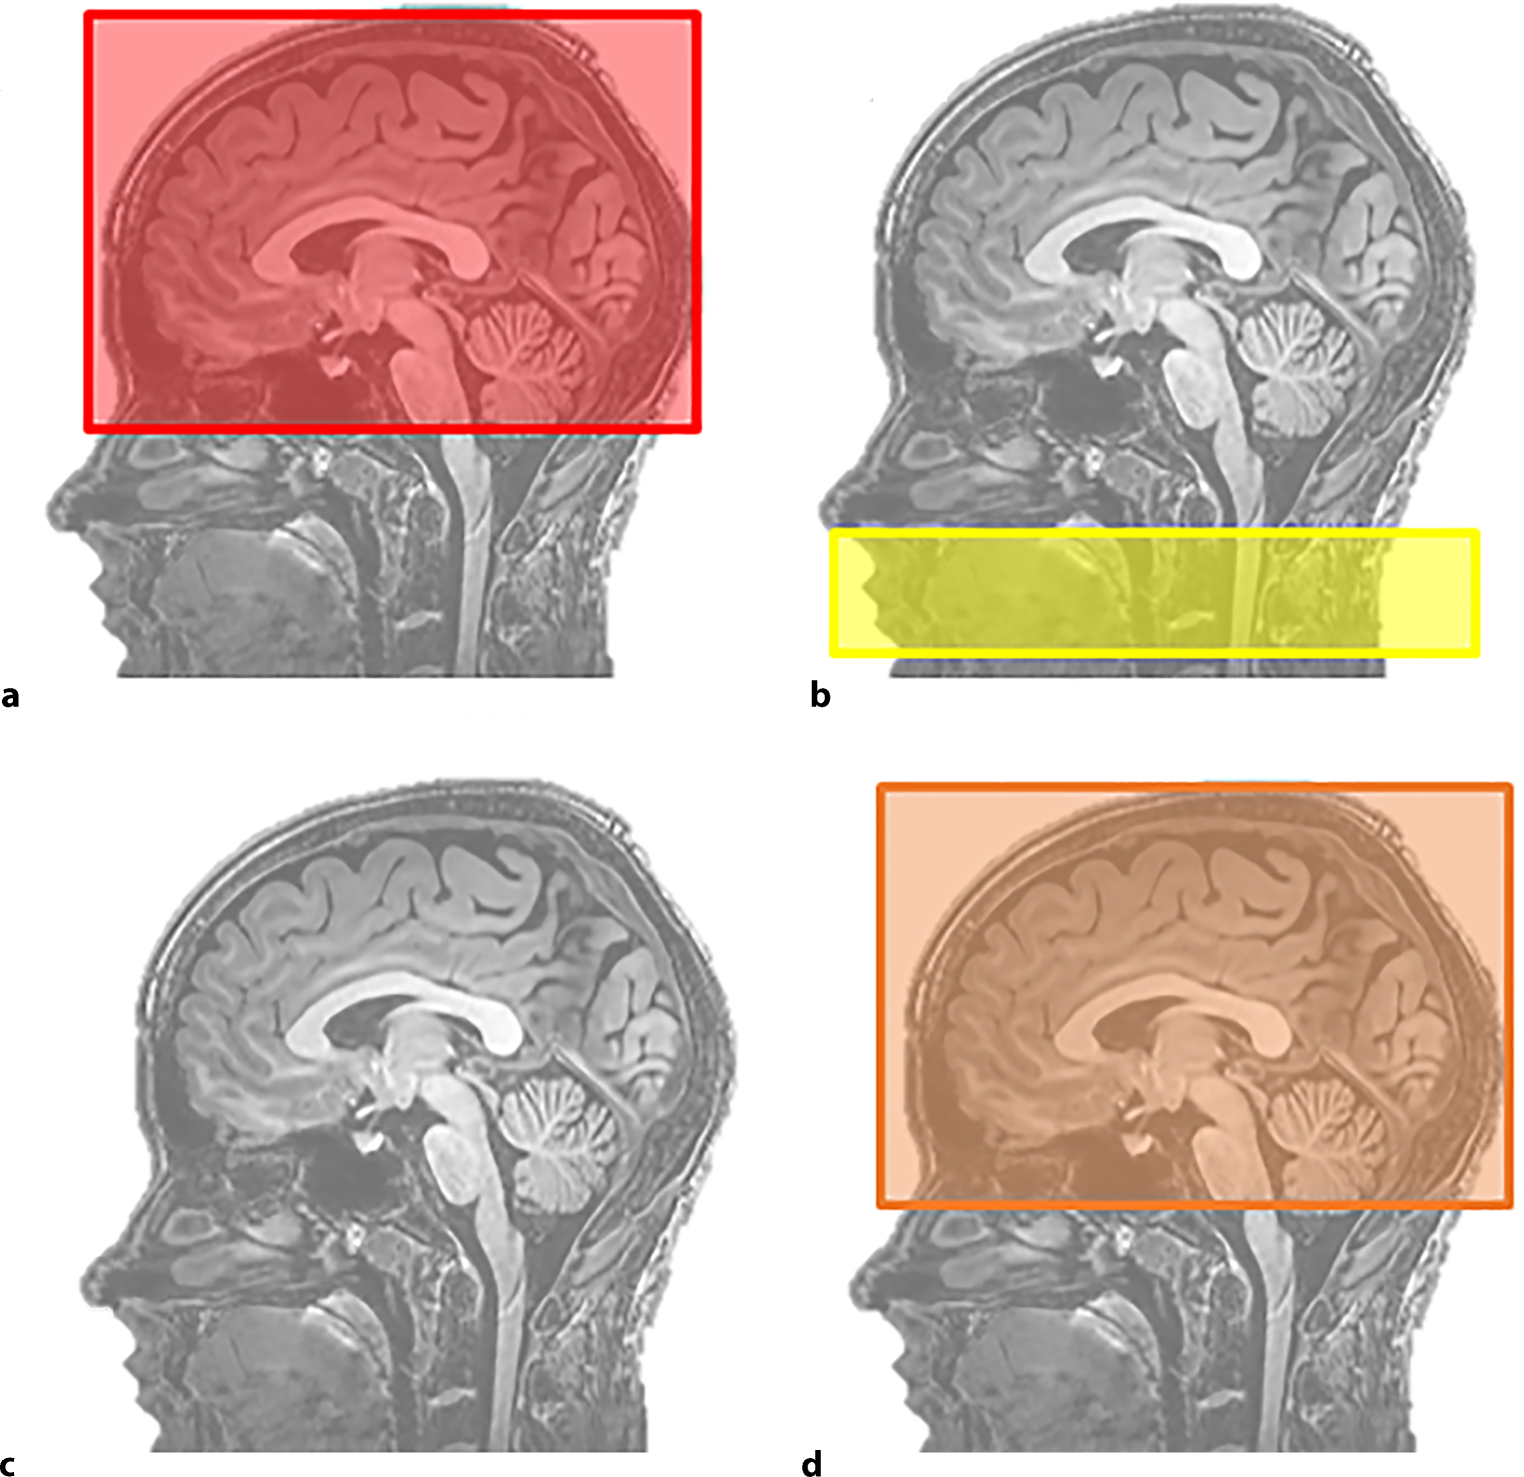

ASL-MRI assesses global and regional CBF (in ml/100 g per min) using an endogenous tracer [17]. The blood will be magnetically labelled in the carotid artery, creating a labelled image and control image. Both sequences include measurements of the static brain, and the difference between these sequences is the magnetisation of inflowing blood. The ASL-MRI acquisition is shown in Fig. 3. Time of day during scanning, room temperature and visuo-auditory stimuli will be kept similar during baseline and follow-up visits. Patients will be instructed to refrain from caffeine for 3 h and from alcohol and smoking for 12 h prior to the scan [18]. ASL-MRI analyses will be performed by an independent core laboratory using pipelines, which are blinded to clinical data and whether scans were performed at baseline or follow-up. Analyses are corrected for brain volume and partial volume effects.

Fig. 3

Arterial spin labelling magnetic resonance imaging acquisition. a Unlabelled scan, b endogenous tracer labelling in carotid artery, c labelled blood enters cerebral circulation and d labelled scan. Cerebral blood flow = labelled scan—unlabelled scan